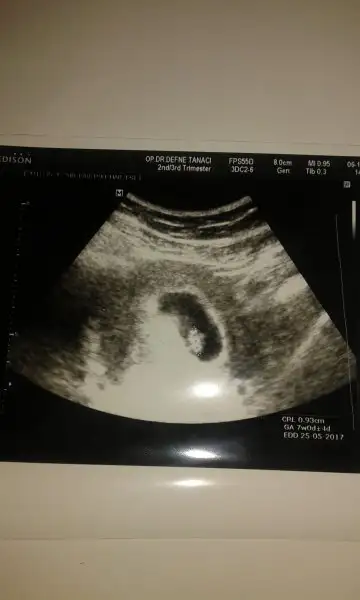

5.5 yaşında oğlum var.bundan evvel haziranda bi gebeliğim sonlandı.8.5 haftada kalbi durdu.şimdiki gebeliğimde hergün kan sulandıcı iğne yapıyorum kendime.inşallah sağ salim kavuşurum yavruma.

Senin oglum keseye göre tutmus buda kiz bence cünkü teori sende tutuyo :)Karından usg.ilk foto 6+3 ikinci foto 7 haftalık.

6 ile 8 hafta arası usg görüntü varsa gönder.arkadaşlar yorum yaparlar.hayırlısı olsun